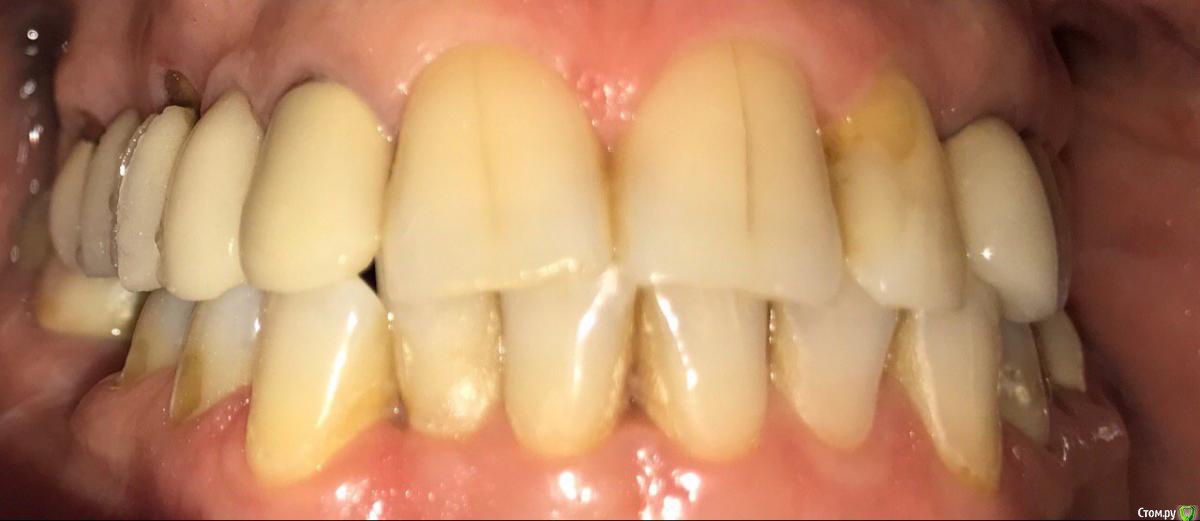

ksenistom Опубликовано 13 декабря, 2016 Поделиться Опубликовано 13 декабря, 2016 Пациентка И.,55 лет,хочет голливуд на обеих челюстях,в виде циркониевых коронок,справа сверху снят мостовидный протез,где установлены 2импл. неделю назад и удалён ретинированный клык в обл 13зуба(фото панорамы нет),поэтому эту сторону пока не трогаем,в области 46 планируется имплантация, 36зуб-вкладка+коронка,в области скученных нижних зубов сделан воксап.Вопрос в том,с чего начать?! Ссылка на комментарий

krokomot Опубликовано 13 декабря, 2016 Поделиться Опубликовано 13 декабря, 2016 нужна понорама, что с высотой окклюзии? Снимите оттиски и регистратор положения верхней челюсти с лицевой дугой, сделайте wаx-up на все! зубы, проведите мокап примерочный и на ношение временный, пластмассовый или композитный, на времянках отработайте окклюзию затем можно гворить о постоянных конструкциях. Ссылка на комментарий